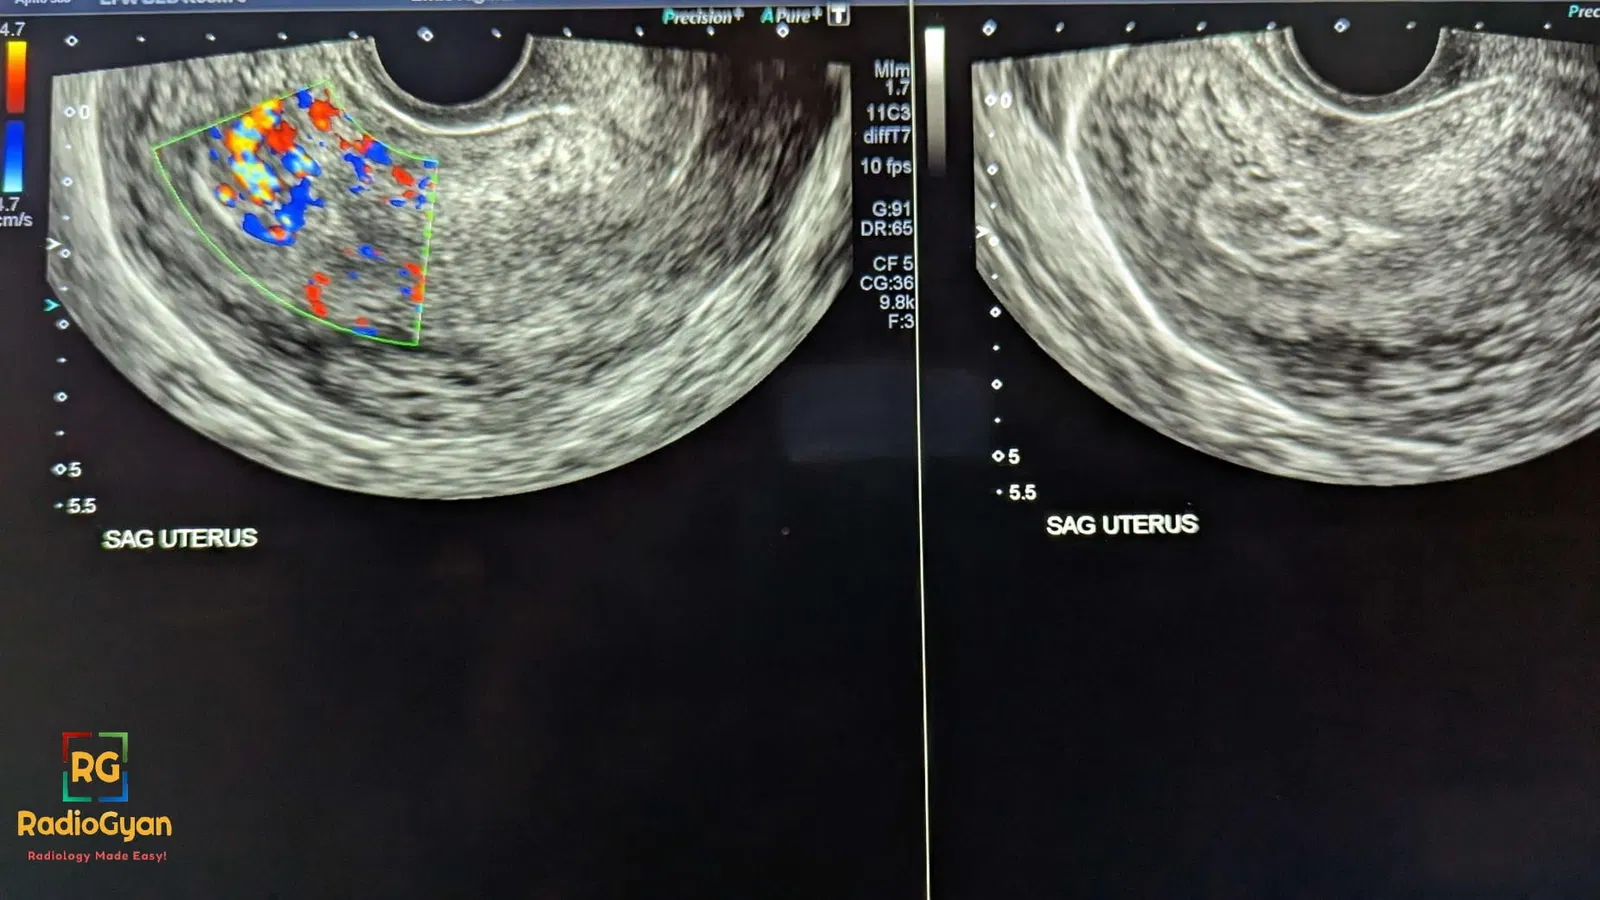

- Ultrasound ( gray scale):

- Increased endometrial echo complex. (8 to 13 mm)

- Intrauterine mass.

- Doppler:

- Vascularity seen from myometrium extending towards endometrium. ( not isolated to myometrium)

- Absence of doppler has low negative predictive value ( RPOC can be avascular)

- The degree of vascularity of the intrauterine component can be compared with the myometrial vascularity in the same image section and graded as type 0, 1, 2, or 3.Refer Gutenberg classification for more details. A schematic representation is as follows: